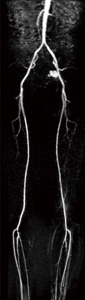

また,造影タイミングをあまり考える必要のないTRICKS-XVの特徴を生かして,造影剤の投与を3回に分けてTRICKS-XVを3回適用し,最も必要とするフェイズのデータをMIP処理することで,広範囲の造影MRAを確実かつ高画質で提供することも可能である(図7)。

図7 3回のTRICKS-XV撮像による腹部〜下肢動脈撮像(画像ご提供:市立旭川病院様)

図7 3回のTRICKS-XV撮像による腹部〜下肢動脈撮像

(画像ご提供:市立旭川病院様)